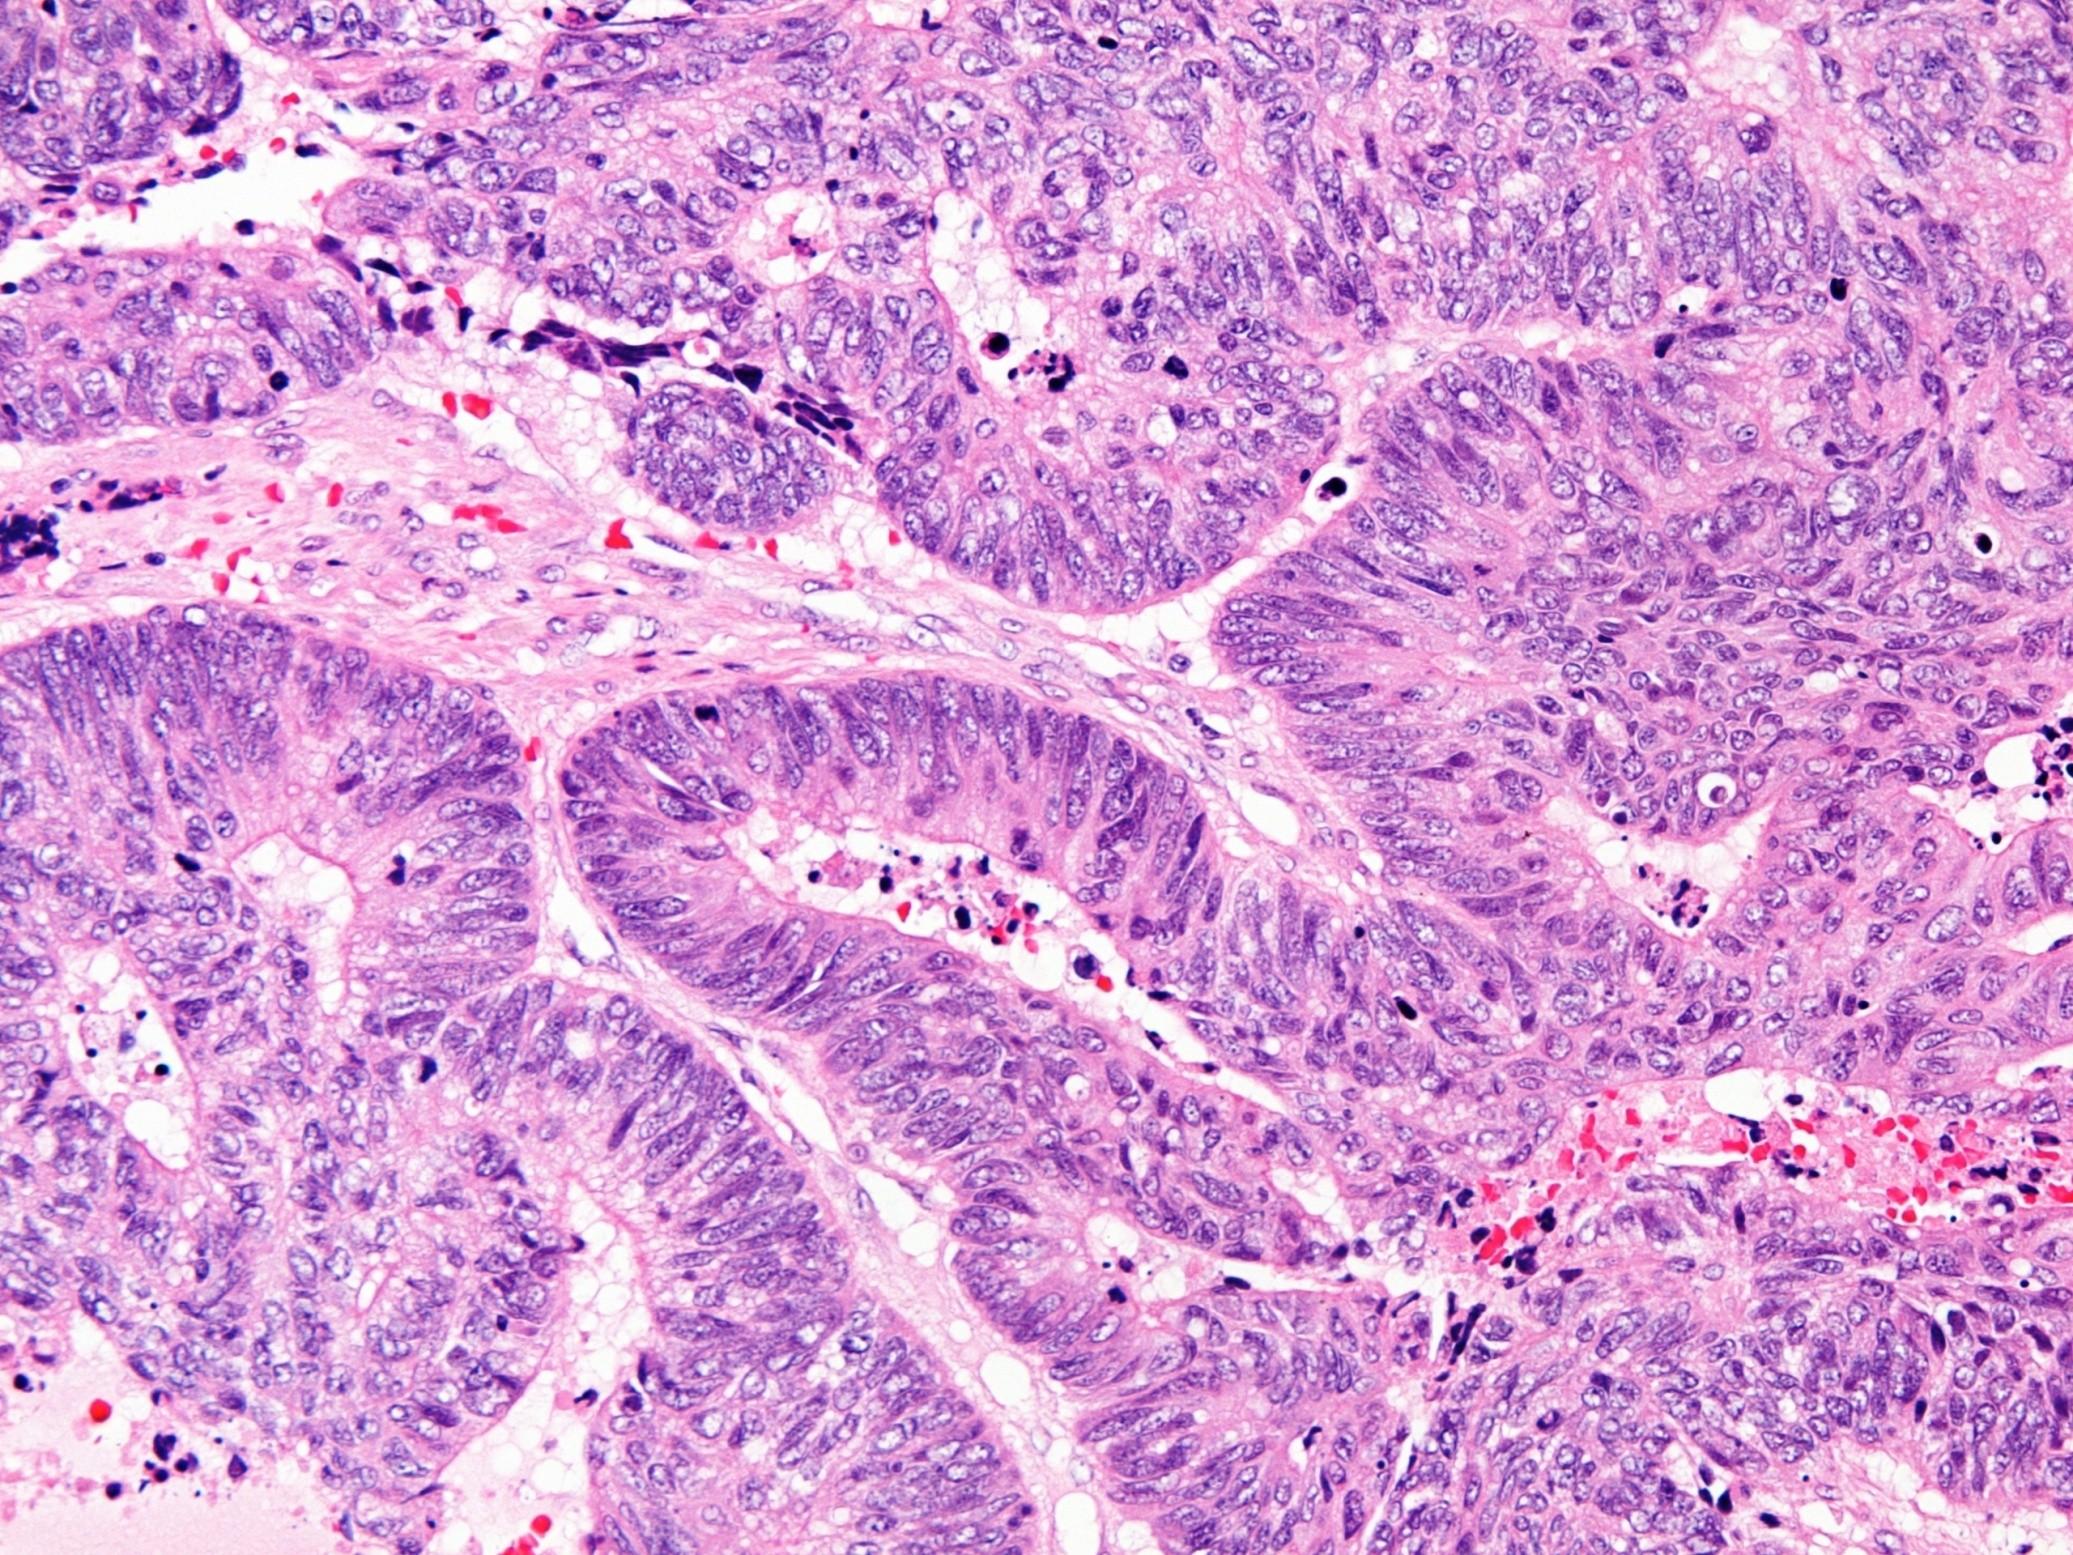

Acinic cell carcinoma

In it’s simplest form

Sheets of large polygonal cells with abundant granular basophilic cytoplasm, small eccentric nuclei with even chromatin pattern

Often nested organoid pattern

Other cell

types

 Clear cells

 Non-specific glandular cells

 Hobnail cells

 Vacuolated

 Architectural arrangements

Solid

Papillary cystic

Microcystic

Follicular